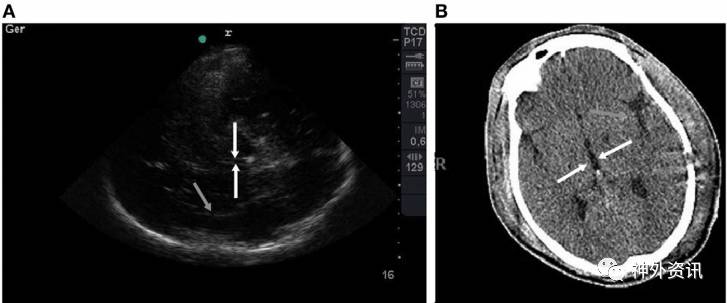

该研究共纳入15例患者,TCCS均在颅脑CT扫描前6h完成。比较患者进入ICU后的第1次CT扫描与TCCS结果。通过Bland-Altman法和评估组内相关系数(>0.75认为相关性强)分析二者一致性。15例患者中男性占80%,平均年龄为42±23岁,GCS评分为5。测量中线偏移,颅脑CT与TCCS结果的平均差异为0.30±2.1mm(组内相关系数:0.93,p<0.01)。第三脑室宽度测量,二者同样表现出极强相关性(0.88,p<0.01)。一致性分析显示,Bland-Altman法未表现出系统偏差。同时,与颅脑CT扫描相比,TCCS对判别非受压所致的中脑周围池和大脑外侧裂改变的精确度较高(图1、2)。

图2. A图中TCCS的白色箭头对指的是间脑平面第三脑室,灰色箭头指向大脑外侧裂,与B图中 CT扫描结果相对应。